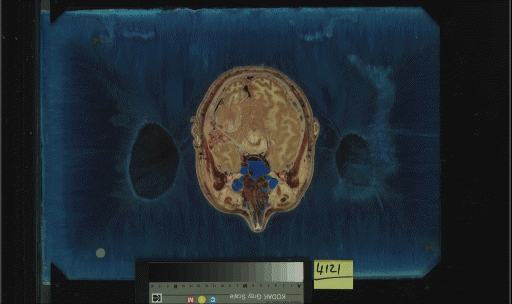

The skin and muscle models were extracted from the cryosection slice data from the Visible Human Project

male dataset. Below, an example slice from the dataset is pictured. The cryosection data was chosen for

a number of reasons. First of all, muscle does not show up well (or at all) on CT scans. Muscle tissue

is easily segmented from the rest of image by simply searching for red. Secondly, the skin was distorted

in the CT scans in the area of the nose. When they "zoomed in" to get higher resoltution images of the

brain, the area of the nose was outside the scanner's field of view. As you can see in the second image,

the nose remains perfectly intact in the cryosection data.